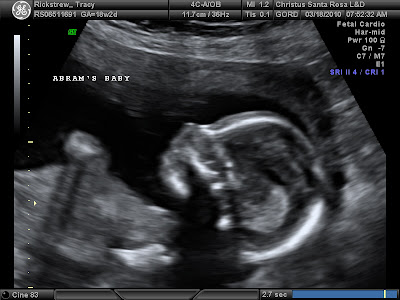

3d Ultrasound Santa Rosa

An Indepth View From Within A Little Insight 3d 4d Ultrasound